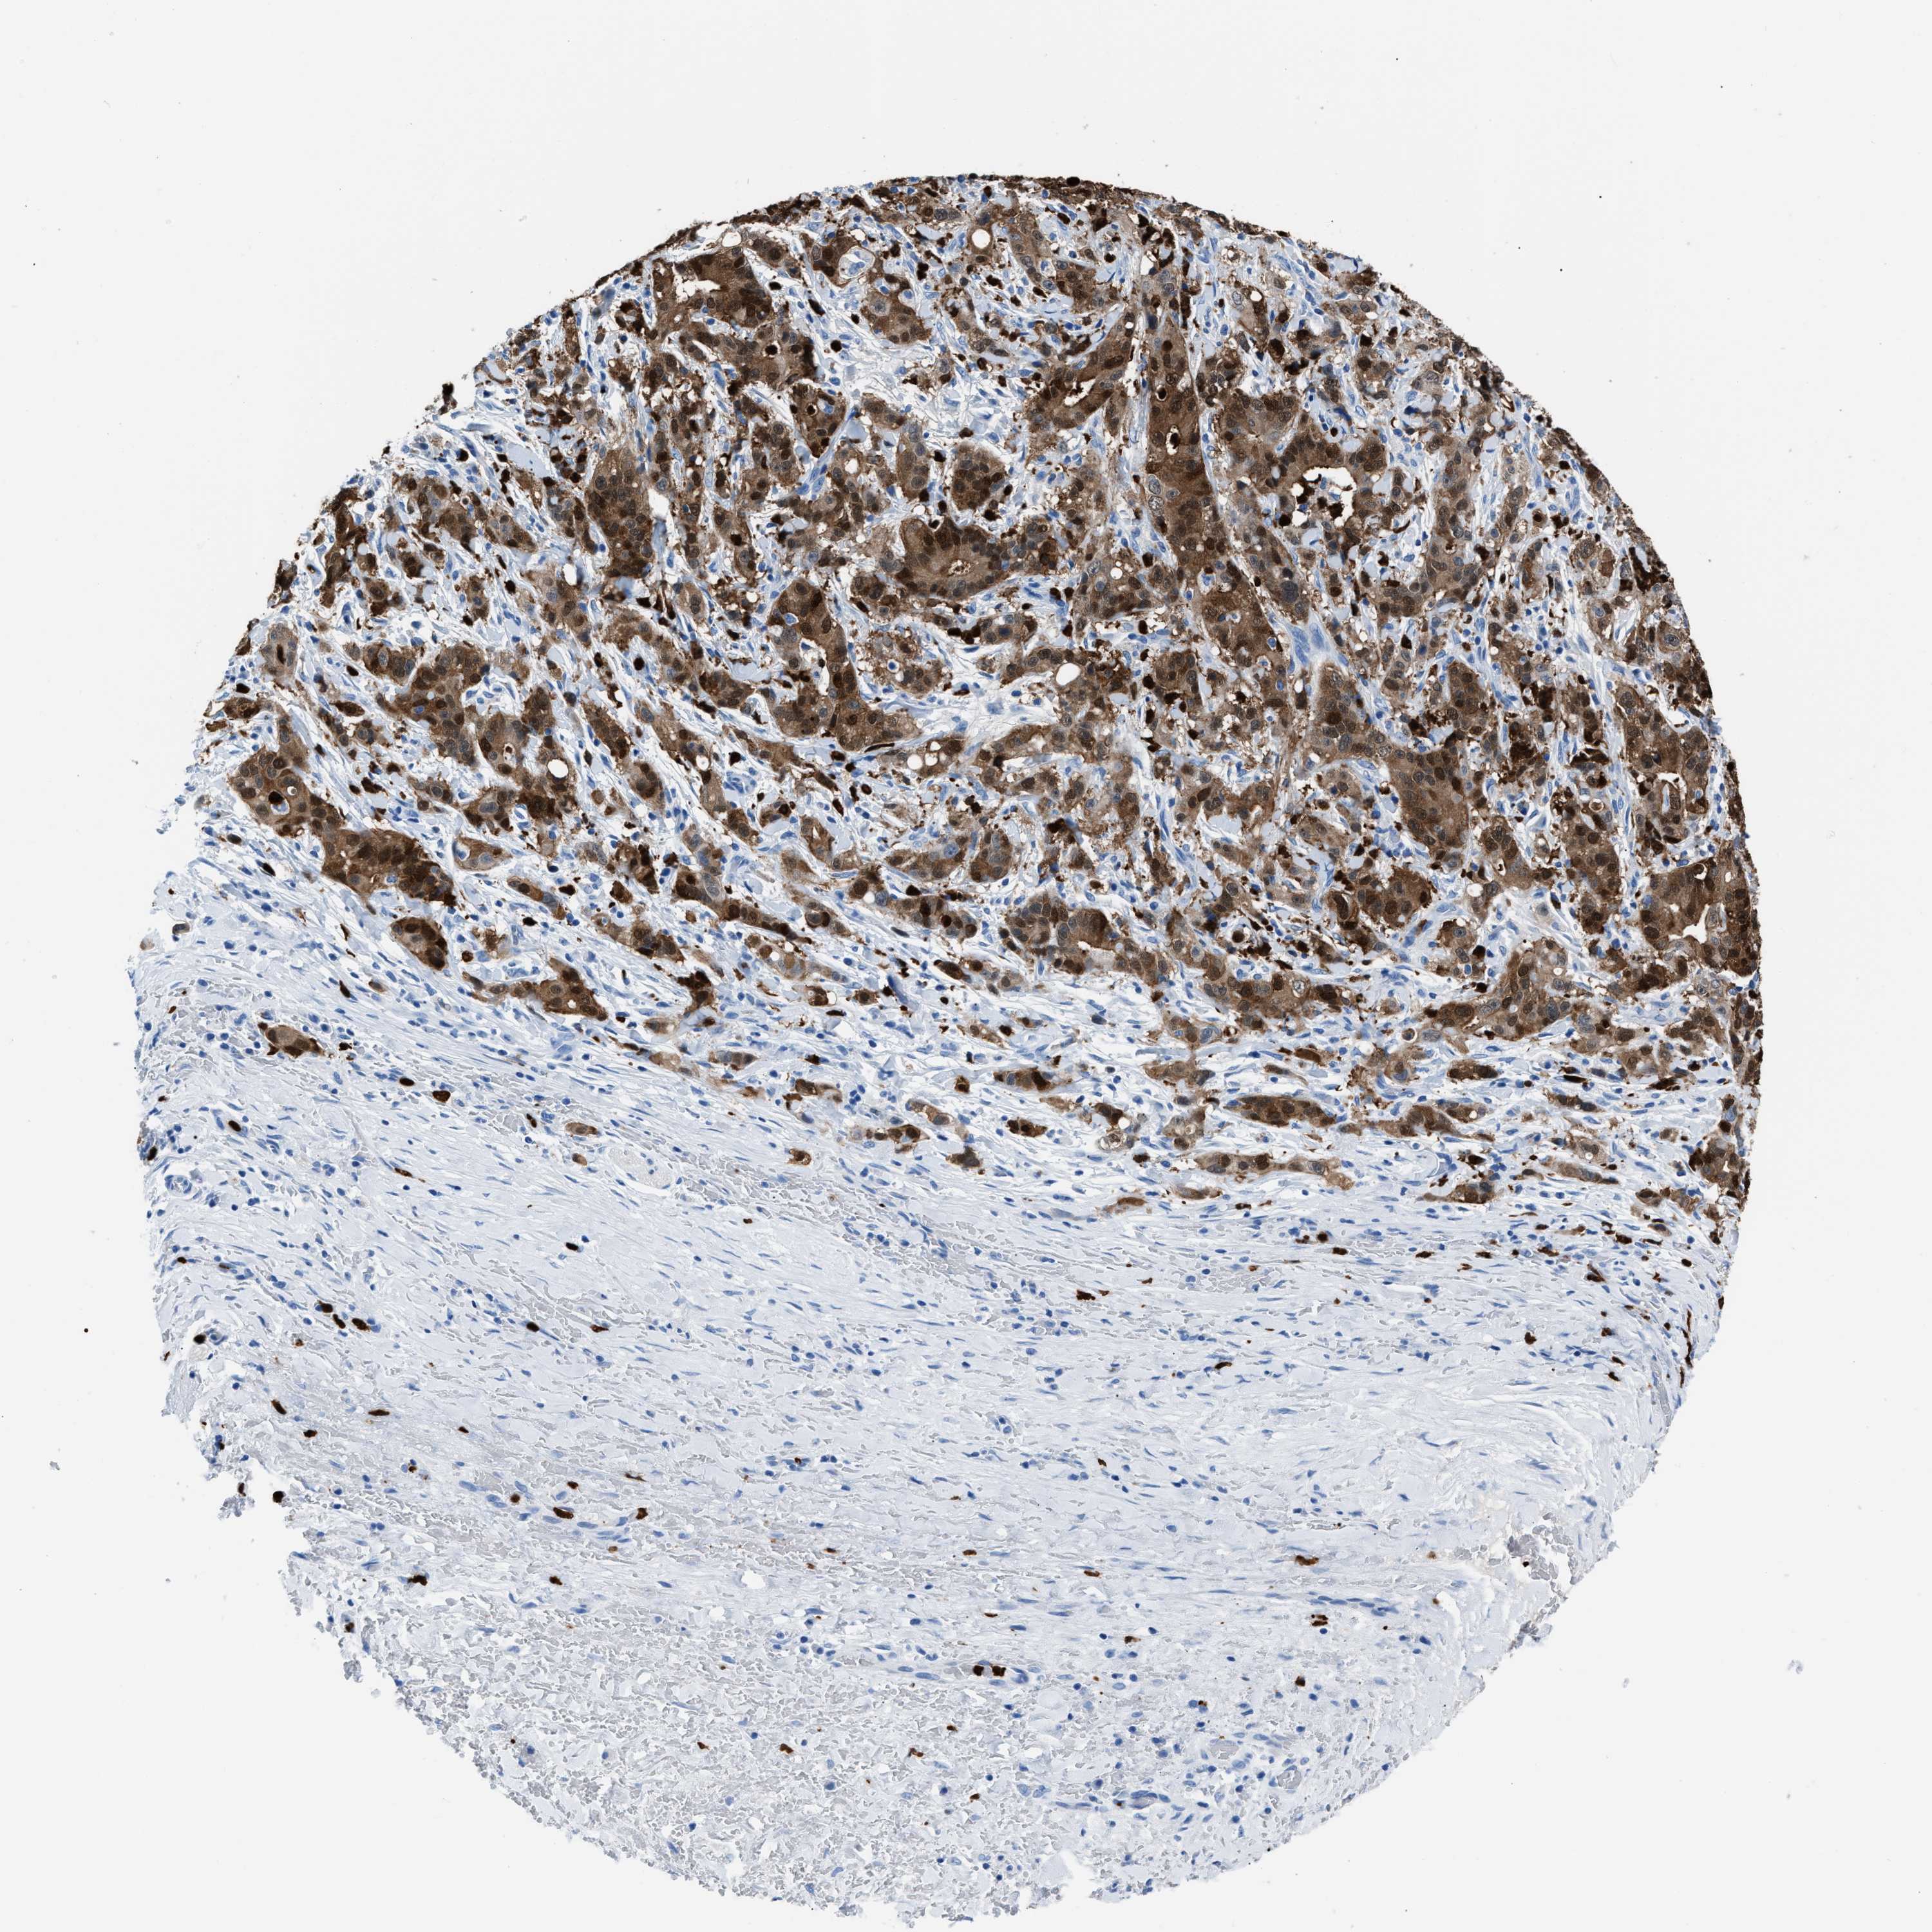

LIVER CANCER - Protein expressioni

A mouse-over function shows sample information and annotation data. Click on an image to view it in a full screen mode. Samples can be filtered based on level of antibody staining by selecting one or several of the following categories: high, medium, low and not detected. The assay and annotation is described here.

Note that samples used for immunohistochemistry by the Human Protein Atlas do not correspond to samples in the TCGA dataset.

Antibody stainingi

Antibody staining in the annotated cell types in the current human tissue is reported as not detected, low, medium, or high, based on conventional immunohistochemistry profiling in selected tissues. This score is based on the combination of the staining intensity and fraction of stained cells.

Each image is clickable and will lead to virtual microscopy that enables deeper exploration of all samples and also displays staining intensity scores, fraction scores and subcellular localization as well as patient and tissue information for each sample.

Antibody HPA019502

Staining

High

Medium

Low

Not detected

Intensity

Strong

Moderate

Weak

Negative

Quantity

>75%

75%-25%

<25%

None

Location

Nuclear

Cytoplasmic/membranous

Cytoplasmic/membranous,nuclear

Cholangiocarcinoma

Carcinoma, Hepatocellular, NOS